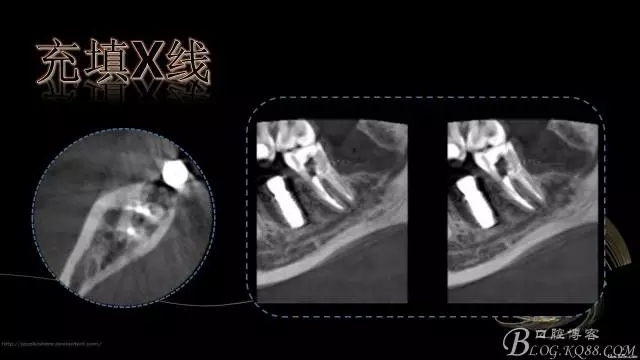

行走在神經(jīng)管上的根管治療